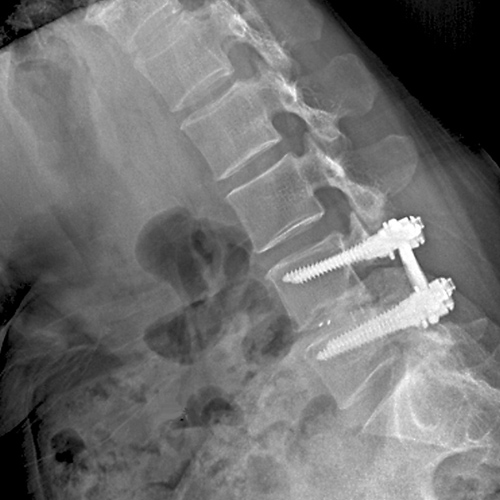

척추고정술

척추관 협착이나 기타 변형으로 인해 불안정한 척추를 스크류로 안정화시켜 수술 후 조기 보행과 유합율을 높여 줍니다.

협착증이 있는 부분에 요추 후궁절제술로 척수신경을 충분히 풀어 준 다음에 척추의 불안정증을 교정하기 위하여 기구(스크류)를 이용하여 척추를 고정하는 수술입니다.

나사못과 금속 기구를 사용하여 불안정한 척추 분절을 단단하게 고정하고 유합시켜, 척추의 안정성을 영구적으로 확보합니다.

불안정하거나 퇴행된 척추 마디의 움직임을 제거하여, 해당 부위에서 발생하는 만성적인 통증을 근본적으로 해소하는 데 가장 효과적입니다.

나사못 고정과 함께 신경을 압박하는 구조물(인대, 뼈 등)을 충분히 제거하여 신경 통로를 넓히는 감압 효과를 극대화합니다.